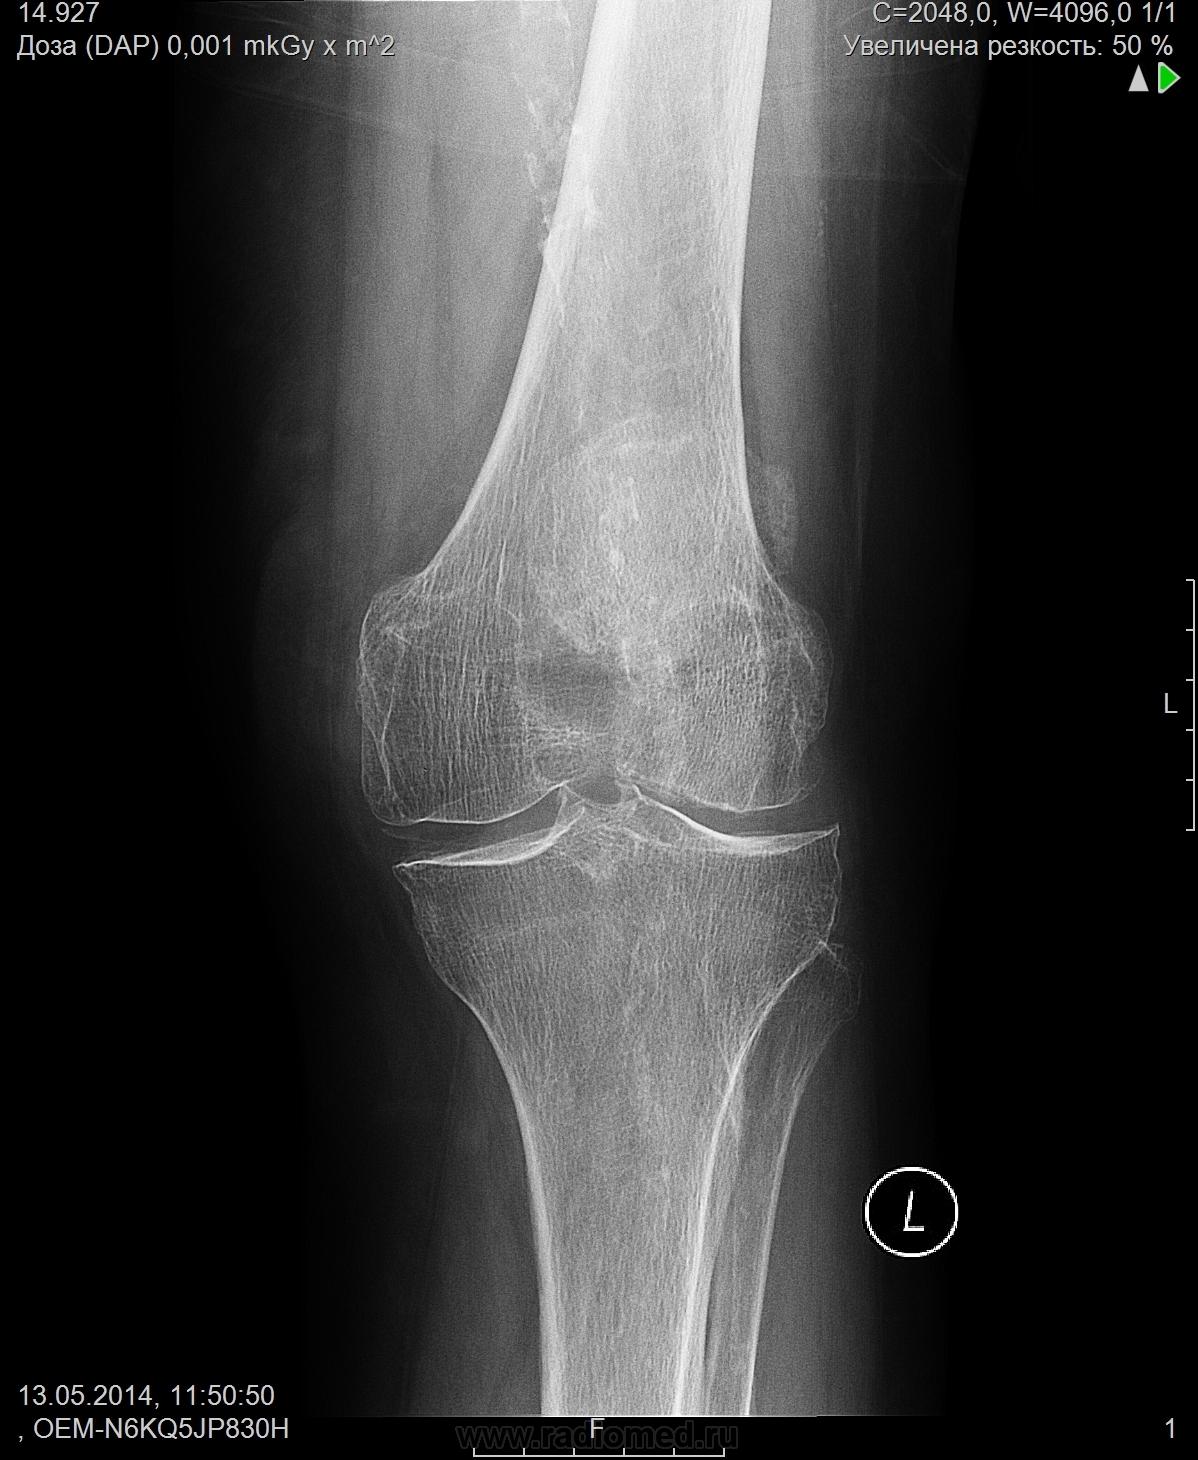

Участок вдавления в области дистального метаэпифиза бедренной кости (может быть последствие диффузного остеопороза?) Пациентке 87 лет. Есть обызвествление межмыщелковых бугорков, обызвествление стенок сосудов. Артроз пателлофеморального сустава.

Полагаю, то это участок м.б. следствием постоянного давления из вне какого-то мягкотканного образования ( как раз Ваша стрелка на нём)

Медиакальциноз артерий забыли.

Выполнил бы, вернее, добавил бы боковую, но только прямую. Как-то надколенник просится в эту выемку на бедре. Очевидно 4-хглавую повредили когда-то. Или связку пателлы. Или и то, и другое... Или с возрастом так натянулись мышцы-связки, уплотнились, будто бы накачались.)) А может, надколенниковая сумка когда пострадала и пателлу без неё к кости присосало.) Вариантов много, верный точно один. Вам решать, Вы случая господин.;)